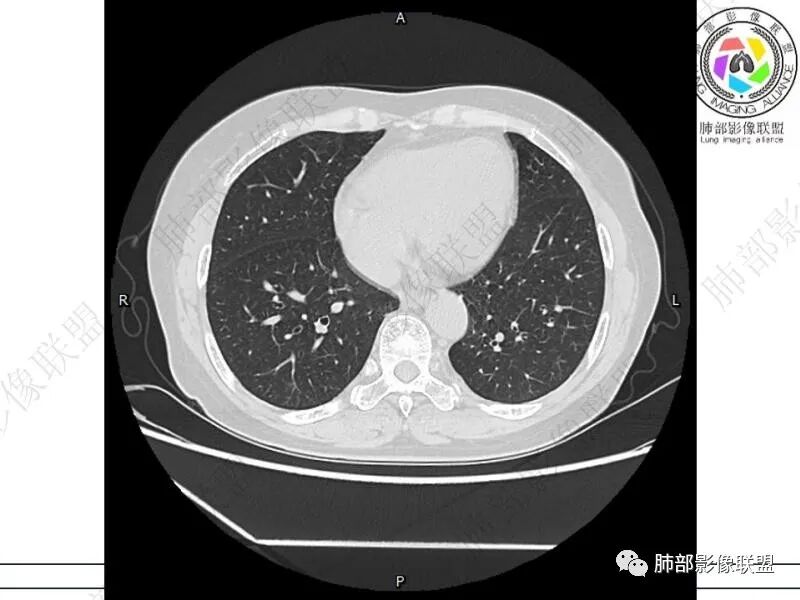

摘星空竹子:两肺胸膜下多发实性结节、磨玻璃影及实变影,短期复查病变有所进展,考虑感染性病变,隐球菌可能,患者有右半结肠癌手术史,转移不能除外。

简单:双肺及胸膜下多发小结节,双下肺胸膜下宽基底团块影,短期内病灶进展考虑炎性病变,隐球?患者ca术后,双肺小结节随诊除外转移

丽:双肺下叶胸膜下多发片状高密度影,边缘模糊不清,内可见支气管穿行,病变长轴平行于胸膜,考虑感染性病变,隐球菌

媛:肠癌术后,免疫力低下。两肺胸膜下结节及实变影,实变影长轴平行于胸膜,密度均匀,边界偏清,周围有晕征,短期复查进展,虽隐球菌荚膜抗原检测阴性,还是考虑隐球菌,鉴别OP

谢加平:结肠癌术后史,两肺胸膜下多发结节及斑块实变病灶,实边边界平直征(亚急性和慢性病变过程),双肺下叶后基底段胸膜下为甚,与胸膜平行特点,见支气管充气征,边缘模糊的GG0,首诊2022年11月18日肺部CT,与治疗11月28日对比,病灶未吸收,双肺下叶胸膜下病灶有侧向融合特点,综合分析符合炎性肉芽肿,隐球菌感染。

老年女性,结肠癌术后。两下肺胸膜下为主片状实变,右下肺短期复查融合且病灶长轴平行于胸膜,实变内可见支气管充气征,边缘磨玻璃晕,另两肺内胸膜下散在数枚小结节状、楔形实性灶。考虑感染性病变,隐球菌可能,鉴别肺转移。

2.影像特征:双肺胸膜下多发实性结节、磨玻璃影及实变影,胸膜下优势分布、晕征、胸膜下脂肪间隙存在,部分病灶边界平直征,有侧向融合趋势。